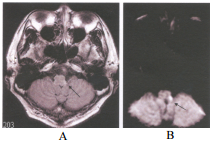

74. 一位 58 歲女性,最近二天發生講話困難、吞嚥困難、步態輕微不穩,根據此二張 MRI 之 FLAIR(A) 以及 DWI(B)影像,此病患最可能的診斷是:

(A) multiple sclerosis(MS) (B) pyramidal syndrome (C) wallerian degeneration (D) Wallenberg syndrome A B